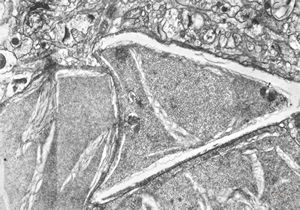

F,50y. | progressive multifocal leukoencephalopathy- viral particles in a glial cell